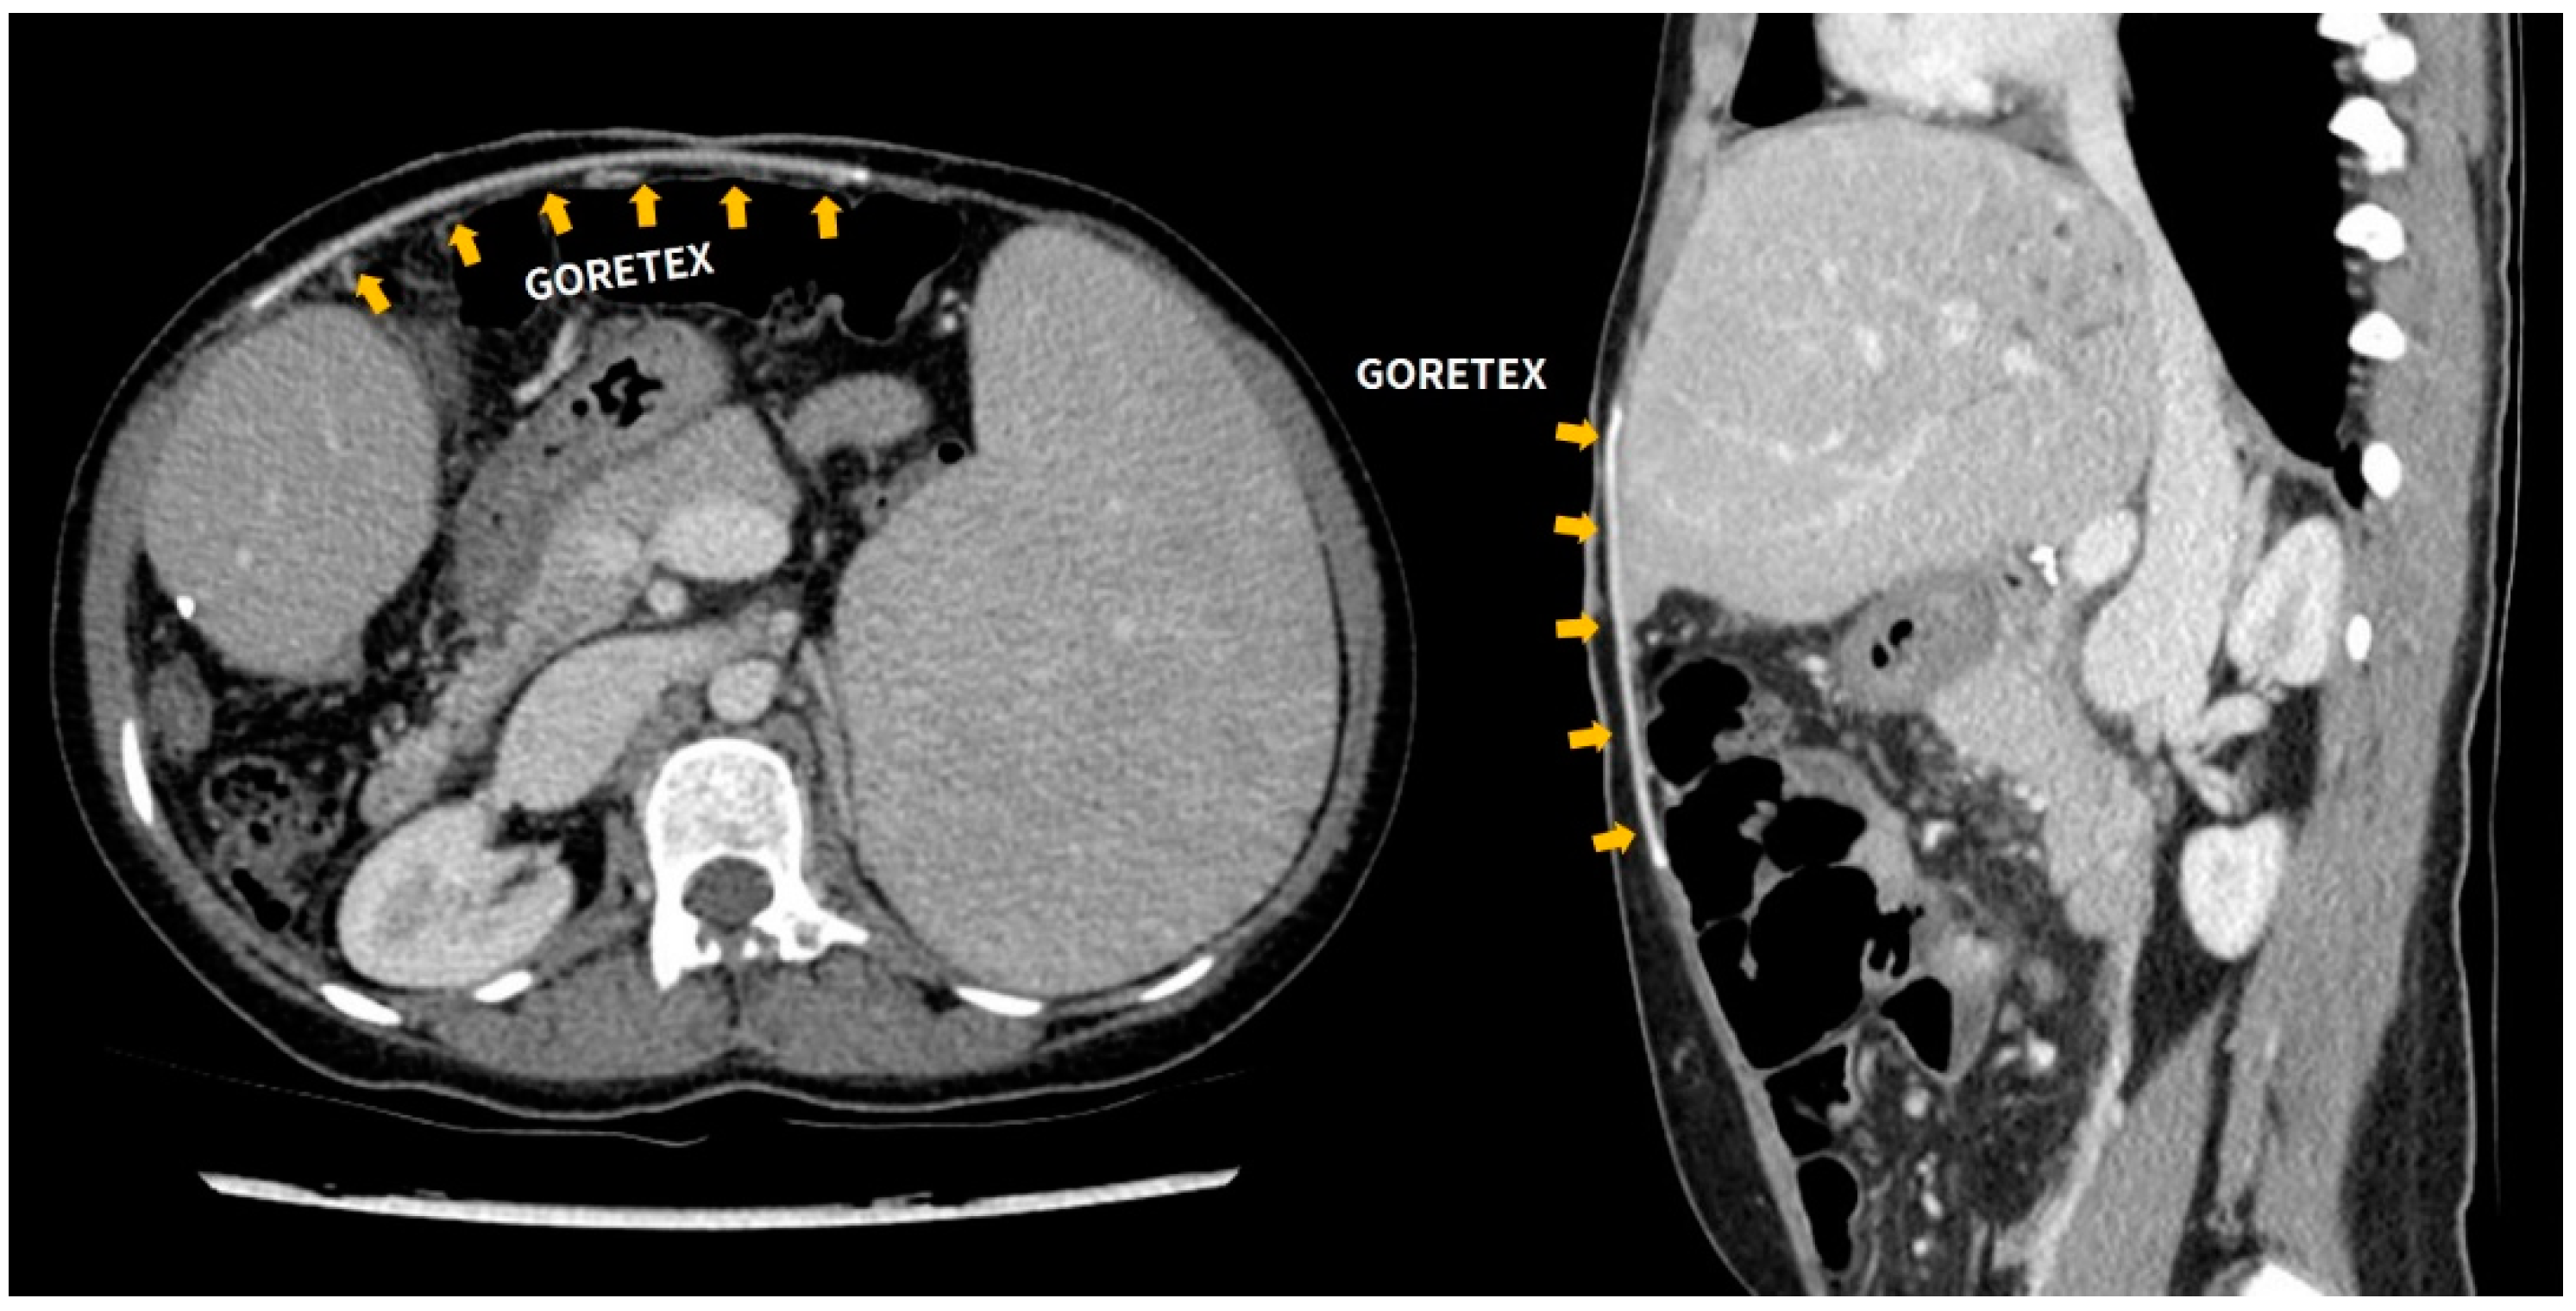

2.1. Surgical Technique for Abdominal Wall Reconstruction with ePTFE (Gore-Tex)